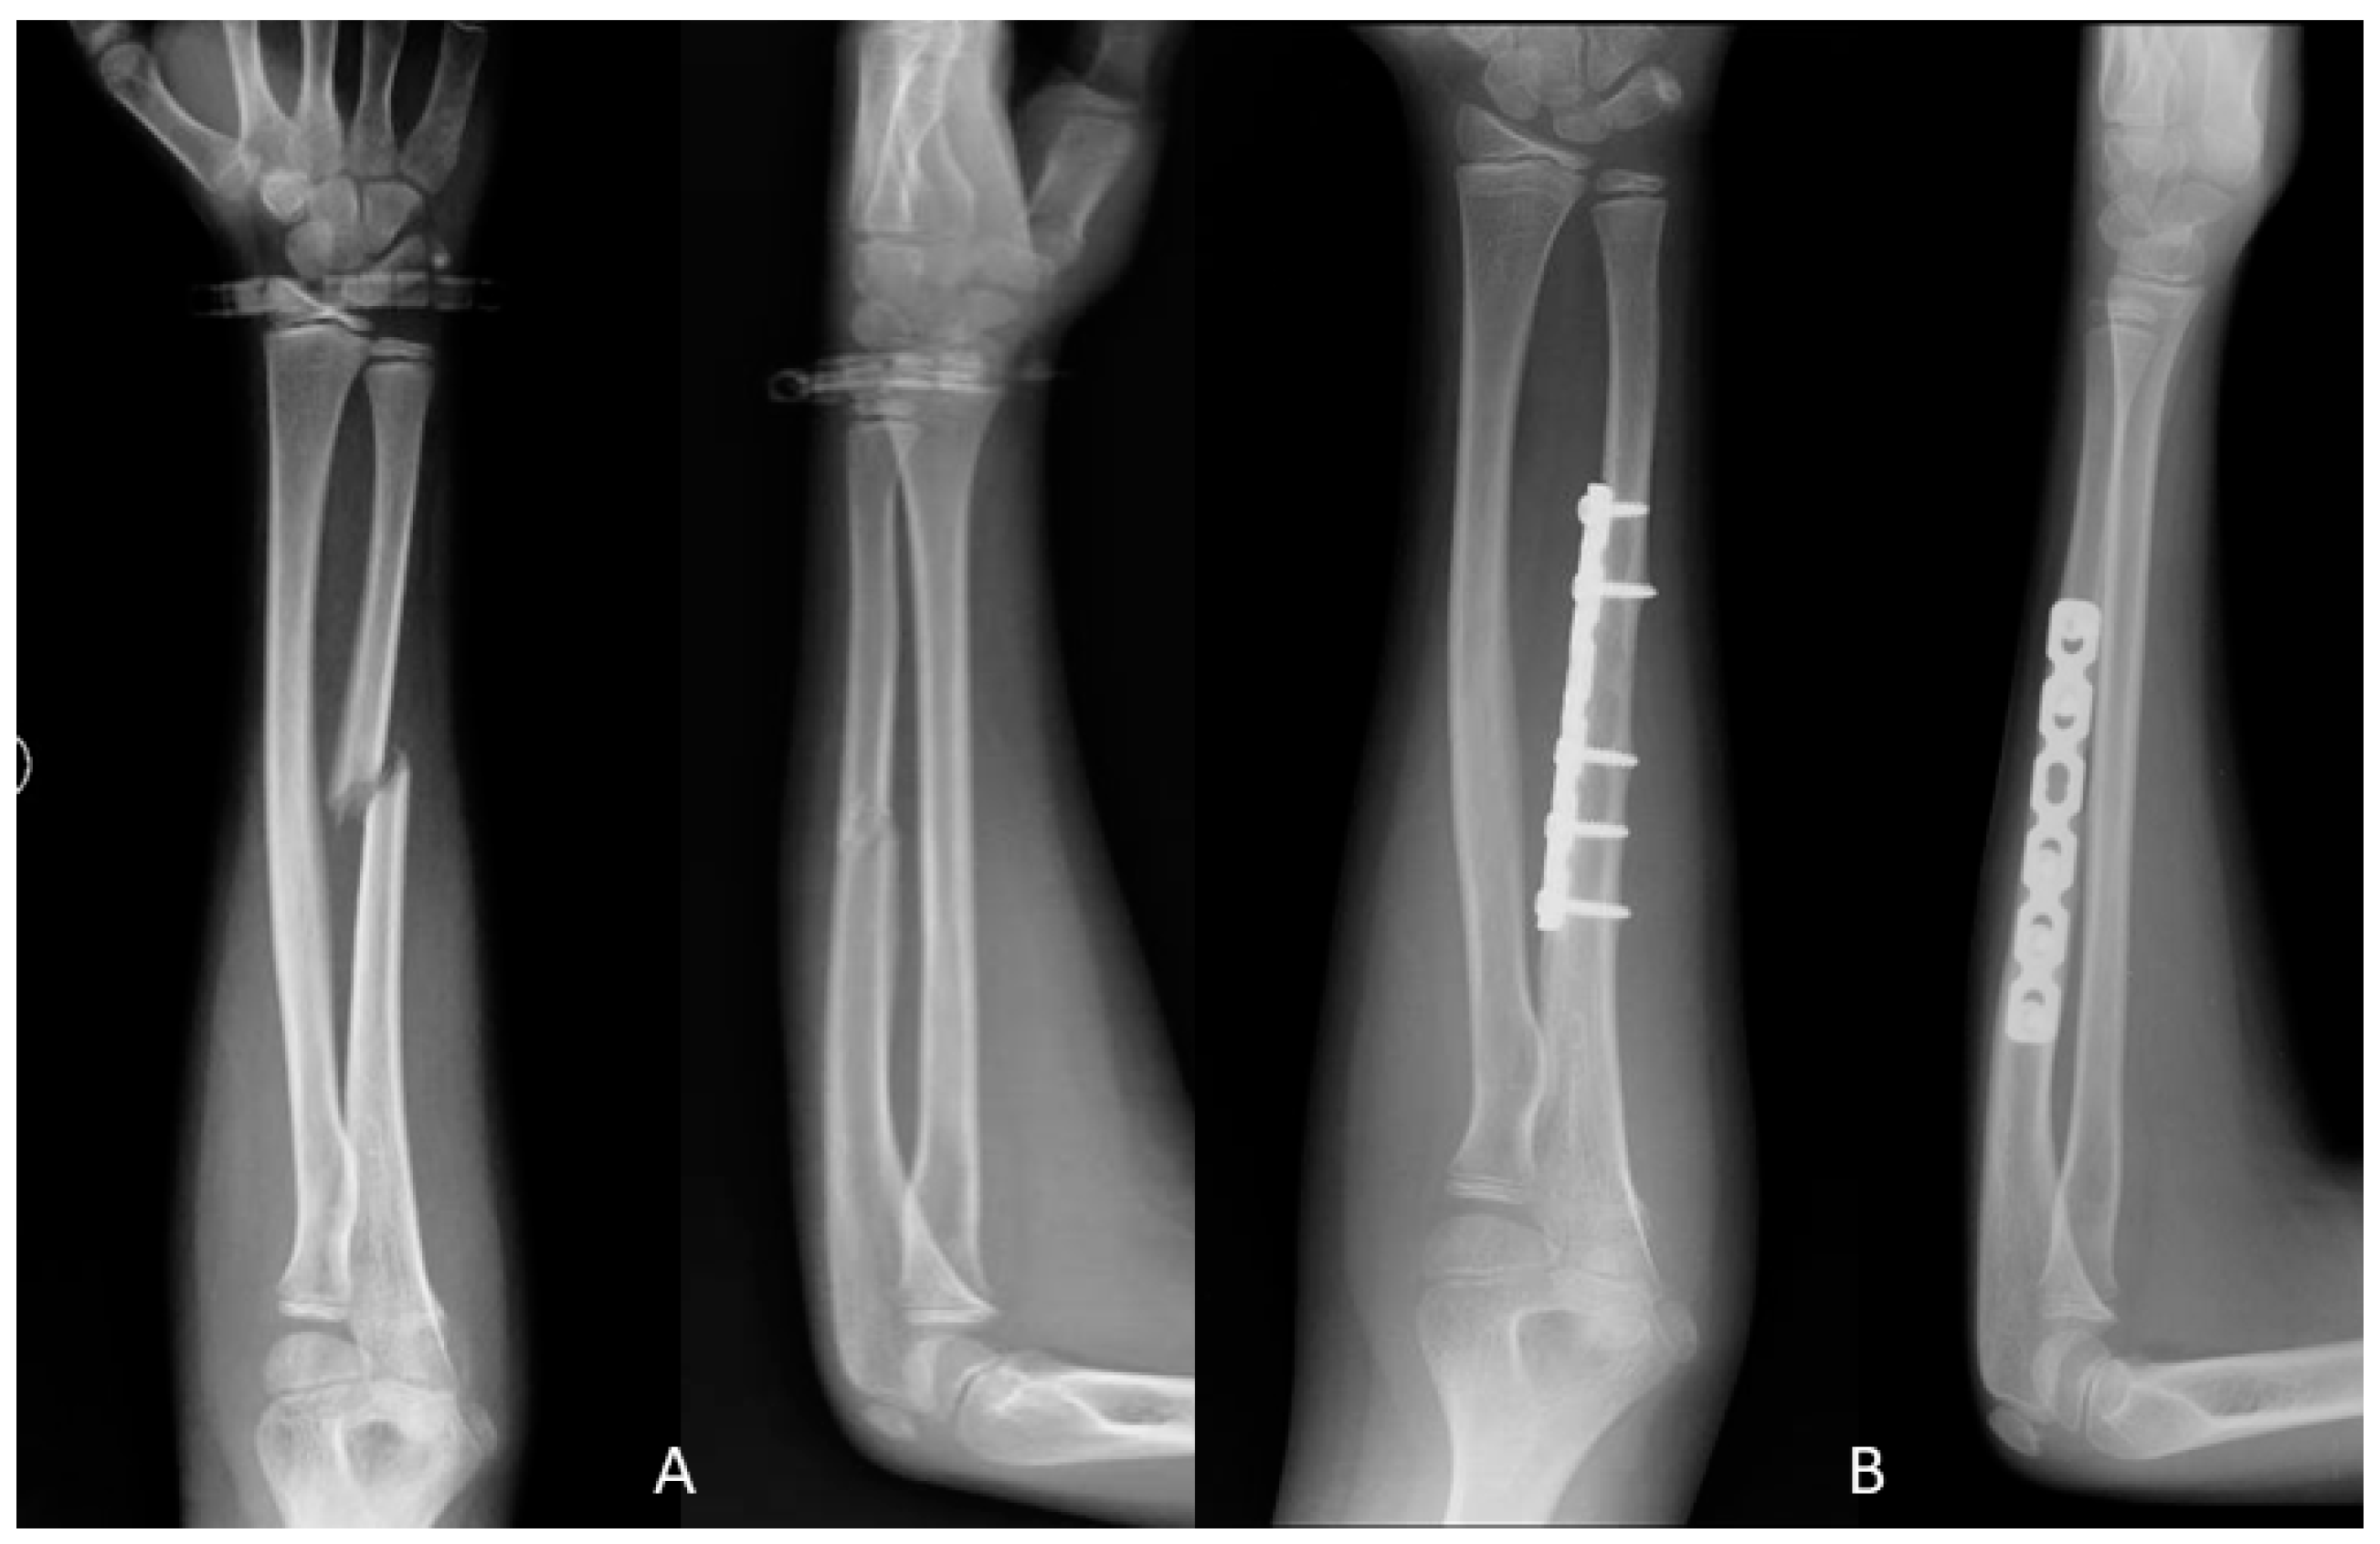

2.2. Surgical Techniques

2.2.1. Open Reduction and Internal Fixation (ORIF)